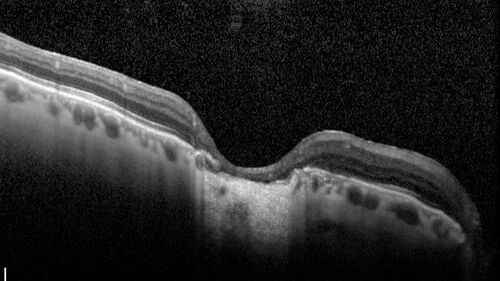

Dome Shaped Macula Left Eye

73 year old female Diagnosed with POHS in the past and treated with laser in the right eye in 1994 with vision loss.  She moved from Tampa to Largo in 2017 and started seeing Dr. Cohen.  She had her last injection in the left eye 2015 prior to moving to Largo.  She has been treated intermittently in the left eye and has been resistant to Anti-VEGF injections.  Her vision is good in the left eye. Images are from April 2023 one month following a Vabysmo injection in the left eye.

VA 20/200 OD, 20/25 OS